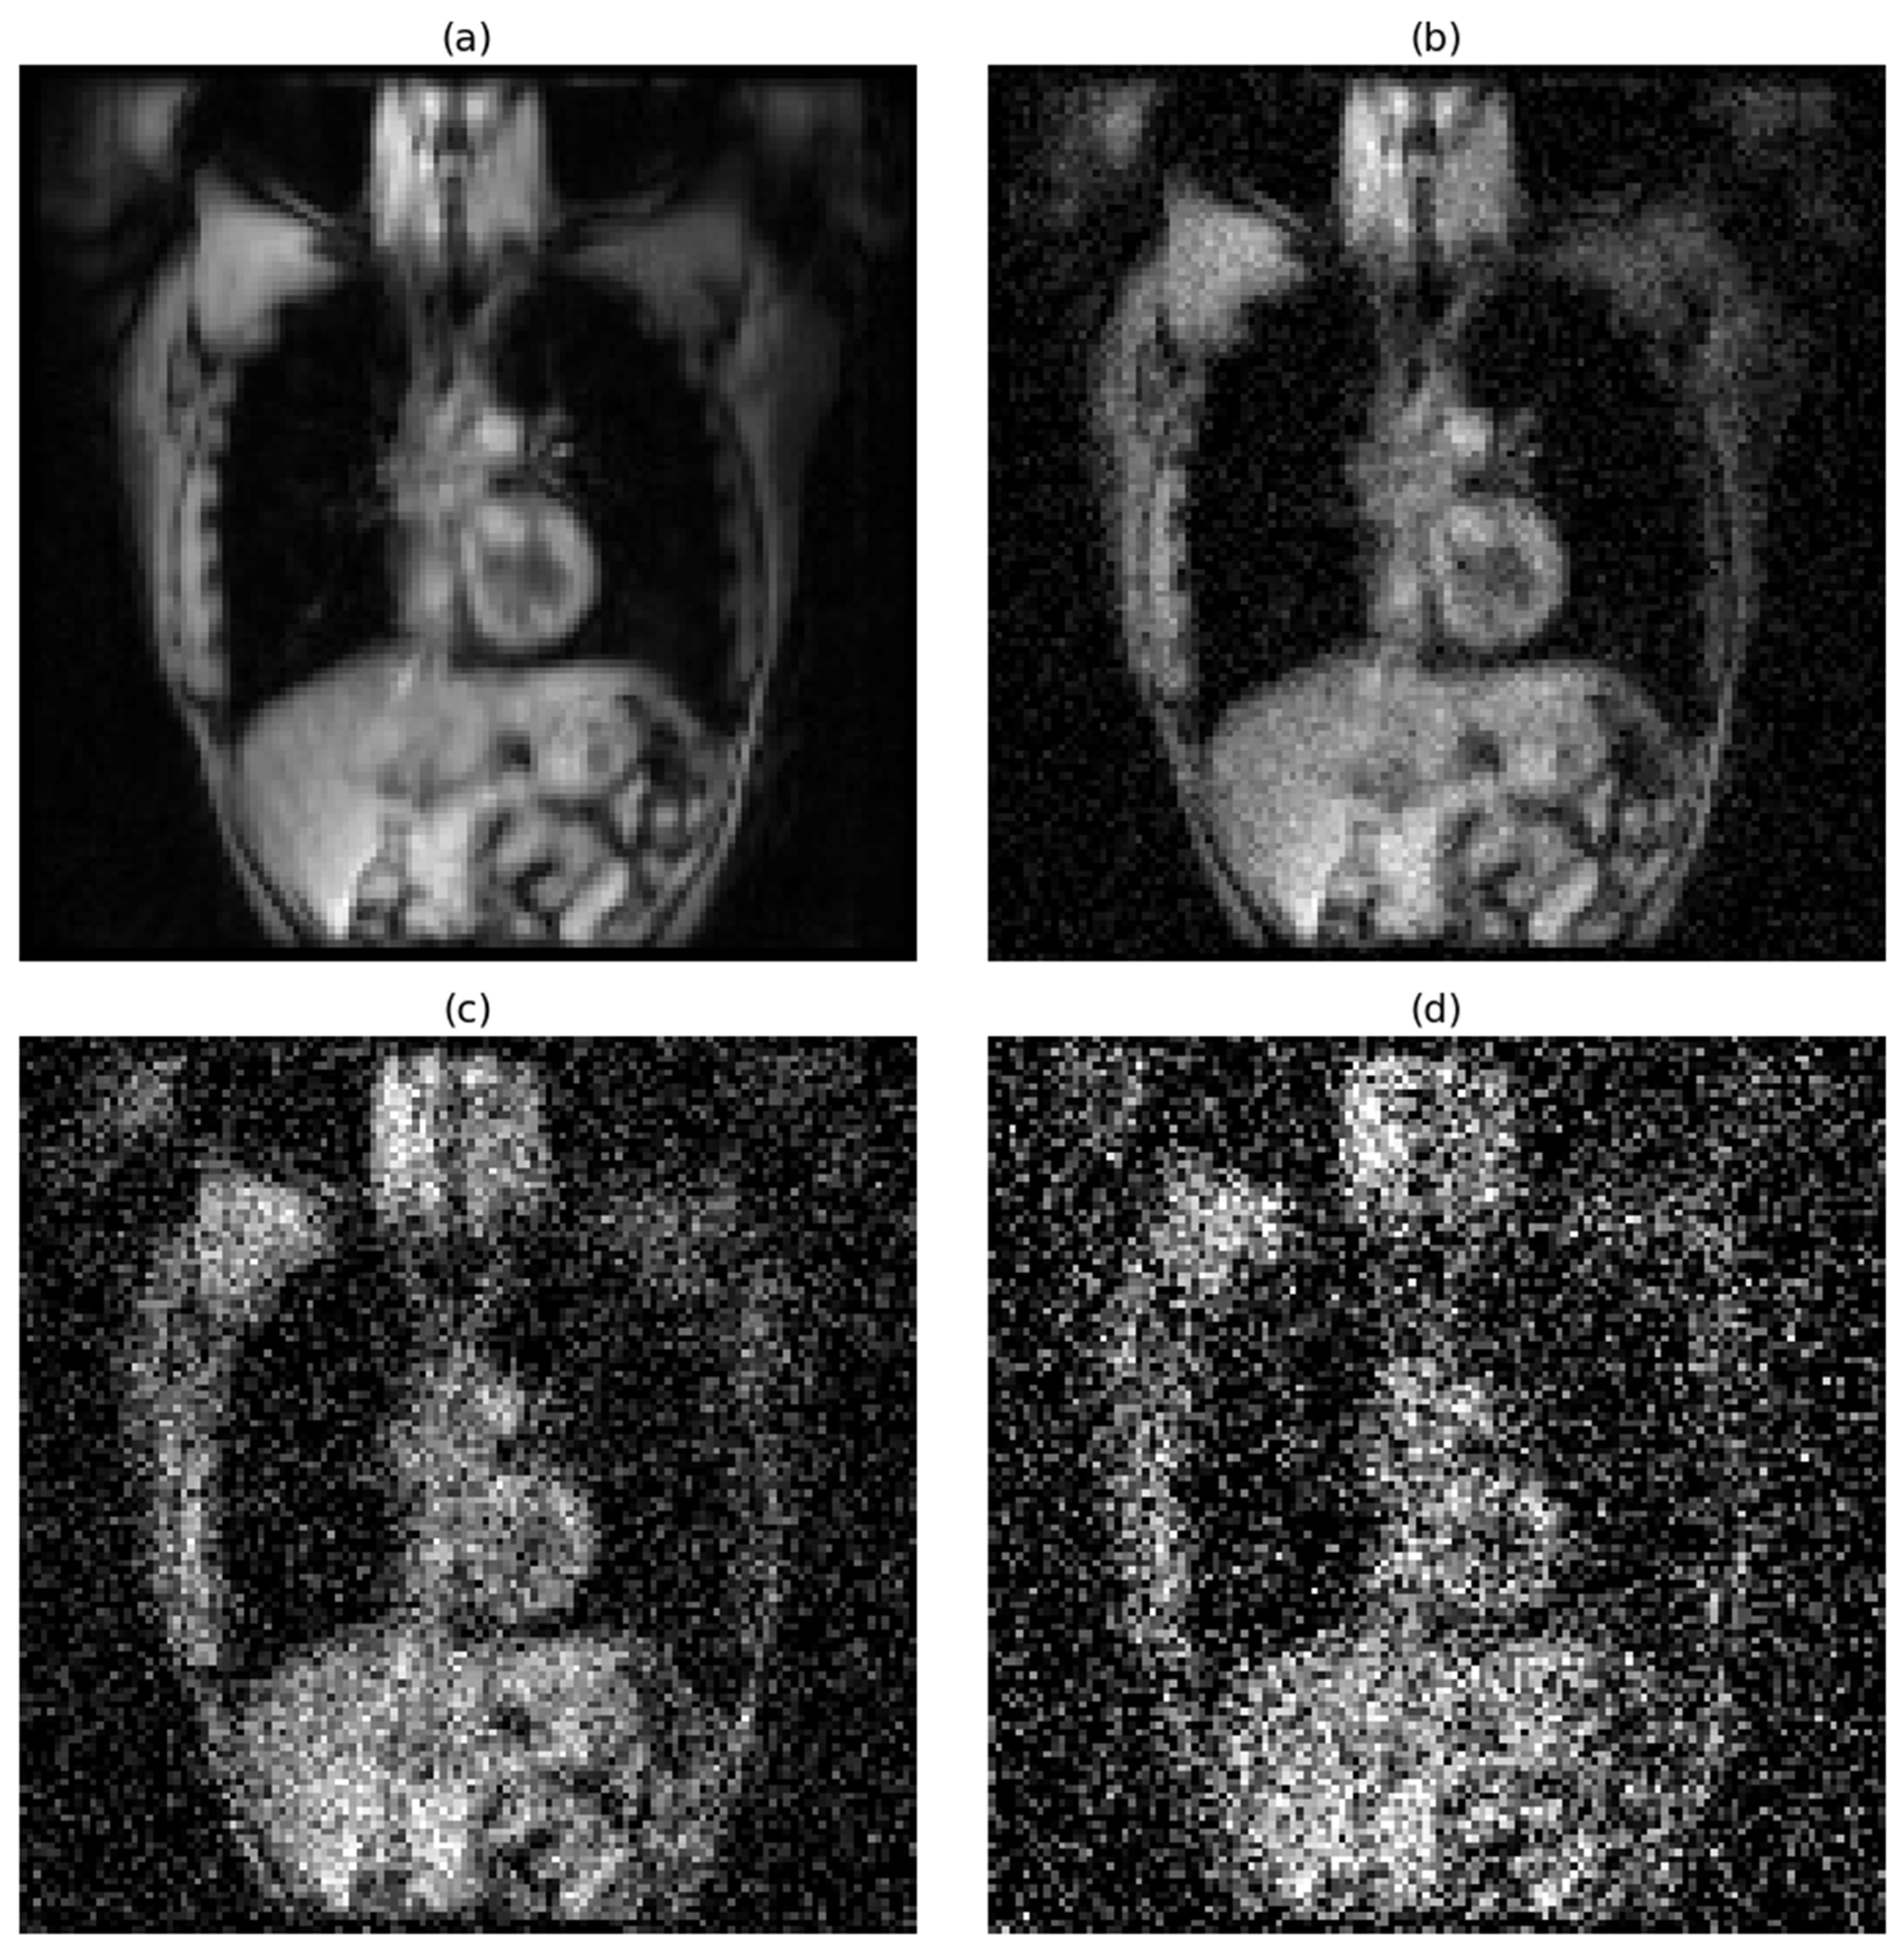

The effects of progressive noise addition on image quality are visually demonstrated in Figure 1 for hyperpolarized gas MRI and Figure 2 for proton MRI.

Figure 2.

Progressive degradation of proton MRI image quality under varying noise conditions. Representative coronal slice demonstrating the impact of increasing Gaussian noise levels: (a) original image without noise (SNR = 59), (b) low-level noise with a standard deviation of 0.05 (SNR = 16.23), (c) medium-level noise with a standard deviation of 0.15 (SNR = 6.84), and (d) high-level noise with a standard deviation of 0.25 (SNR = 3.86).